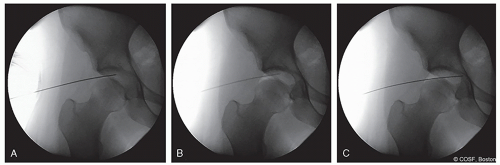

The hip-length 14-gauge needle should enter the skin at the AL portal (Figure 33.8). The typical trajectory that is desired is 10° to 15° cranial and 10° to 15° posterior in order to enter the hip joint as lateral as possible (Figure 33.8A). The space between the femoral head and acetabulum is targeted with the needle tip faced away from the labrum when entering the capsule. This is done with fluoroscopic guidance

The needle trocar is removed, and 5 cc of air is injected as an air arthrogram to confirm joint entry and, in some cases, break the suction seal of the hip and allow continued traction (Figure 33.8B)

The ideal location of the needle is as distal as possible without injuring the femoral head. If the needle needs to be readjusted, the needle should be completely withdrawn and reinserted

A nitinol wire is inserted through the needle and confirmed to stop at the cotyloid fossa. If the wire stops short of the fossa, it is likely that the portal placement is either too anterior or too posterior and should be repositioned (Figure 33.8C)

Figure 33-8 ▪ A, Insertion of needle into distracted hip joint via the anterolateral portal. B, Insufflation with 5 cc of air to confirm entry into the joint. C, Placement of nitinol wire into joint; note that the wire stops at the cotyloid fossa. (Courtesy of Children’s Orthopaedic Surgery Foundation.)